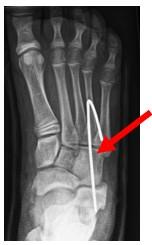

Omdat het hielbot wordt verlengd komt het gewrichtje tussen de calcaneus (hielbot) en os cuboideum (teerling botje) onder spanning te staan. Om die reden wordt een ijzeren pinnetje (K draad) geplaats zodat dit gewrichtje niet uit de om gaat. Het draadje zal 6 weken blijven zitten en wordt tijdens een gipswissel op 6 weken na de operatie verwijderd.

Figuur 4: Röntgenfoto van de voet waarbij we zien dat de K draad (De witte lijn aan het einde vd pijl) in het CC gewrichtje is geplaatst.